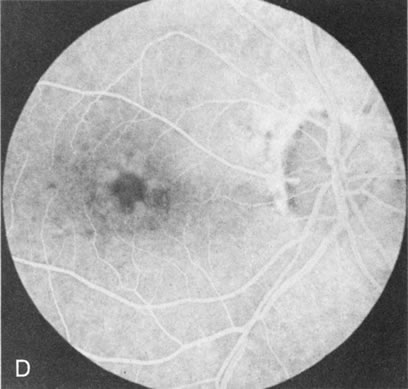

STARGARDT'S DISEASE (FUNDUS FLAVIMACULATUS)

In Stargardt's disease, thes most common hereditary macular dystrophy, FA has a variety of functions. In the mildest fundus presentation, with visual symptoms and visual function out of proportion to the observed maculopathy, FA can confirm or even make the diagnosis and can avoid a mistaken diagnosis of malingering, hysteria, or central nervous system disease (Fig. 9A and B). When a maculopathy is present without surrounding parafoval flecks, FA may show patchy areas of transmission hyperfluorescence in the posterior pole, indicating a more diffuse involvement (Fig. 9C and D).

Fig. 9. Stargardt's disease–fundus flavimaculatus. The mild maculopathy (without parafoveal flecks) (A) is confirmed by the angiogram (B). The relative absence of the underlying choroidal flush, resulting in an easier visualization of the overlying retinal capillary circulation, has been referred to as the “silent” or “dark” choroid, and is considered a common finding in this disease. The diagnosis is confirmed in an individual with a pigmentary maculopathy without flecks (C). Here the angiogram demonstrates widespread transmission hyperfluorescence and a “silent” or “dark” peripapillary area (D). When the posterior pole shows multiple yellowish-white flecks (E), the angiographic findings do not necessarily correspond to the flecks (F). It should also be noted that despite the widespread abnormalities, the background choroidal fluorescence is normal.

In a large majority of patients (86% in one study),20 there is an absence or decrease in the background choroidal fluorescence (which is referred to as the “silent” or “dark” choroid) (see Fig. 9B). This warrants special attention because it occurs so frequently, is rarely found in other retinal disorders,21 and may be related to histopathology that shows an increase in lipofuscin in the RPE.22